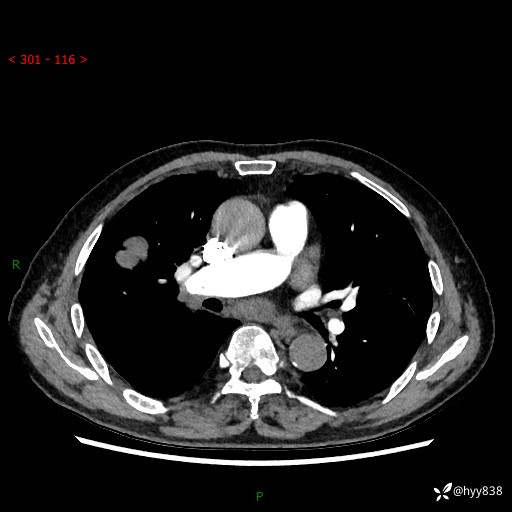

69岁/男,间断咳嗽伴气促、下肢水肿。临床拟诊肺栓,偶发肺均质强化结节--结果公布

【患者信息】:69岁/男

【主诉】:间断咳嗽伴气促、下肢水肿2周

【现病史及既往史】:患者2周来无明显诱因出现咳嗽,咳少量白痰,不易咳出,伴有气促,呈间断发作,症状与活动费力相关,以夜间为甚,不能平躺入睡,偶有憋醒,无胸闷胸痛、无发热、无头晕、头痛等不适,伴有双下肢中度水肿,就诊于当地县人民医院门诊,完善相关检查提示:左下肢深静脉血栓形成,未予以特殊处理,今患者为求进一步诊治来我院就诊,拟“心衰”收入我科。 起病以来,患者精神、饮食、睡眠可,大小便如常,体力明显下降,体重未见明显减轻。

【检查】:胸部CT增强